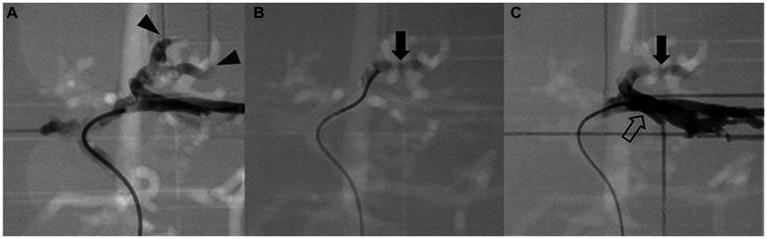

Based on the result, a 3D model of the normal canine hepatic artery and the hepatic tumor was made using one representative case from each group, and despite the models having some limitations in reflecting the exact tactile and velocity of blood vessels, TAE procedure was successfully simulated using both models.